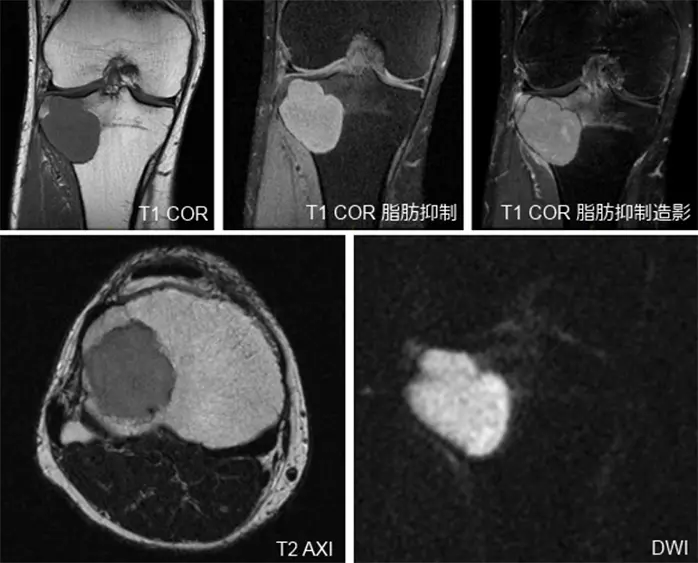

画像所見

受診時の膝関節X線画像では,右脛骨の骨幹端から骨端に及ぶ骨透亮像が認められ(Figure 1),単純CTで,同様に膨張性に発育する44x40x37mmの溶骨性病変が認められ,関節面まで1mm程度のところまで進展している.硬化縁はなく,内部は筋肉より低濃度で石灰化は認められない(Figure 2).また,右膝関節のMRIでも右脛骨近位外側,骨幹端から骨端線を越えて骨端まで及ぶ44×40×36mm大の病変を認める.内部はT1強調像で低信号,T2強調像で筋肉より高信号でほぼ均一.周囲に軽度の骨髄浮腫を伴い,拡散強調像では高信号を呈している.脂肪抑制T1強調像で高信号であるが,造影後との差分画像で全体が増強されている.以上の所見よりGCTが疑われる(Figure 3).